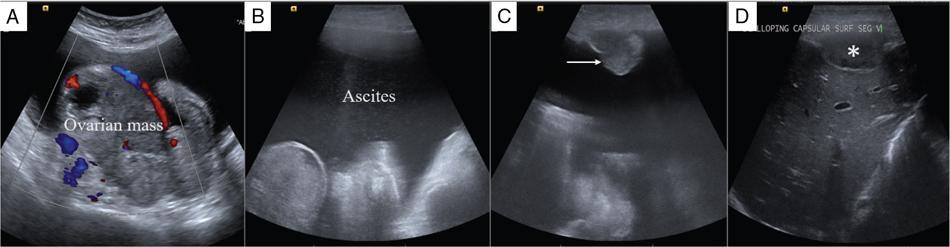

Shivsamb Jalkote, Slesha Bhalja, Disha Lokhandwala, Mansi Jantre, Karthik Ganesan Peritoneum is involved in a diverse group of primary as well as secondary pathologies ranging from the infective/inflammatory spectrum to malignancies. Peritoneal diseases are both common and potentially life threatening, and yet often get neglected in routine evaluation, due to the complex peritoneal anatomy and sometimes subtle imaging manifestations. The radiologist forms an integral part of the multidisciplinary team dealing with peritoneal pathologies and hence, having a lucid understanding of peritoneal anatomy, pathways of disease spread and different treatment options is paramount for an accurate radiological analysis. All three major serosal cavities (pleural, pericardial and peritoneal) of the body are derived from a single coelomic cavity, which is lined by a continuous mesothelium. At 2 weeks of gestational age, during the gastrulation stage, the embryo is a trilaminar disc, composed of the endoderm, mesoderm and ectoderm. During this stage, the development of the coelomic cavity commences as a consequence of morphological changes in the mesodermal cells leading to a coalition of the intercellular spaces. Peritoneum originates from mesoderm with its parietal layer developing from somatic mesoderm and visceral layer developing from splanchnic mesoderm. Initially, the peritoneum is an empty sac into which the growing gut tube protrudes (at 3 weeks of gestational age), resulting in the formation of the dorsal mesentery (formed by the fusion of two layers of the splanchnopleuric mesoderm) by which the gut tube is suspended lengthwise. The mesodermal cells opposed to the gut tube represent the future visceral peritoneum and those lining the body wall and the septum transversum form the future parietal peritoneum. Analogously, the ventral mesentery originates from the mesoderm of the septum transversum with the closure of the anterior abdominal wall, and, is short and not as extensive as the dorsal mesentery. The two mesenteries are aligned in the sagittal plane, subdividing the primitive peritoneum into right and left cavities, which are continuous anteriorly below the inferior edge of the ventral mesentery. With the development of various abdominal organs as buds from the gut tube, the capacity of the abdominal cavity diminishes, pushing the midgut loop into the umbilical cord. This physiologic herniation of the midgut takes place at the 6th week of gestation. Simultaneously, as the peritoneum drapes over the developing organs, there is compartmentalization of the cavity and a pattern of folds develops that eventually form the peritoneal ligaments. The majority of these ligaments arise from the ventral or dorsal mesentery. As the hepatic bud develops within the ventral mesentery, derivatives of the ventral mesentery can be divided based on their relation to the liver. The gastrohepatic ligament (lesser omentum) develops dorsally and the falciform, coronary, and triangular ligaments develop ventral to the liver. Conversely, the dorsal mesentery spans between the gut tube and the posterior abdominal wall, and the spleen and pancreatic tail develop within it. In congruence, it forms the gastrophrenic, gastrosplenic and splenorenal ligaments and peritoneal folds of the small and large intestines. As stated earlier, the dorsal mesentery has a relatively larger caudad extension and since the spleen develops in its upper portion, the rapidly growing mesentery beyond the spleen forms the greater omentum. Finally, the differential growth of the greater curvature of the stomach and the right hepatic lobe results in rotation of the abdominal organs and their mesentery, and the cephalad portion of the peritoneal cavity is divided into a larger ventral cavity, called the greater sac, which caudally communicates with the common peritoneal cavity, and a smaller dorsal cavity called the lesser sac. The key aspects of peritoneal development are summarized in Flowchart 8.6.1 and Fig. 8.6.1. Laparoscopy remains the gold standard in the assessment of peritoneal disease, however, it is an invasive technique, and has certain diagnostic limitations including the inability to assess parenchymal diseases, extraperitoneal diseases, and also has limited utility in the presence of adhesions. Hence laparoscopy is not recommended as the first-line modality and has been replaced by cross-sectional imaging in routine clinical practice. The role of imaging is primarily to assess disease burden in terms of volume and extent and to identify surgically nontreatable disease, which reduces open and shut laparotomies. Peritoneal metastatic disease burden is assessed using peritoneal carcinomatosis index (PCI) both surgically as well as using cross-sectional imaging, details of which will be discussed subsequently. CT, MRI and PET/CT are all commonly used imaging modalities, however, there is no singular universally accepted reference imaging standard for the peritoneal disease. In a recent meta-analysis evaluating the diagnostic performance of imaging in the detection of peritoneal metastasis (PM), authors concluded that MRI (DWI) and PET/CT show comparable diagnostic performance in gastrointestinal and ovarian cancer malignancies however the widespread availability of MRI makes it the more likely imaging modality of choice in the future. The results of this study are summarized in Table 8.6.1. Conventional imaging including radiography and barium studies have a poor diagnostic yield in evaluating peritoneal pathologies. Abdominal radiographs are usually restricted for identifying pneumoperitoneum and bowel obstruction in the setting of acute abdominal pain. Diffuse increase in radio-opacity of the abdomen, poor definition of soft tissue shadows (psoas, liver and spleen), bulging flanks along with medial displacement of small bowel loops from the properitoneal fat stripe are indirect markers of large ascites which can prompt further evaluation with ultrasonography. Indirect features of peritoneal disease on barium studies include mass effect and displacement of adjoining bowel loop, narrowing of bowel loop with bowel dilatation along with nodularity, spiculation, or tethering of adjacent mucosal folds or haustra with sacculation of the uninvolved contralateral border. Barium studies have fallen out of favour in routine radiological practice owing to the widespread use of cross-sectional imaging. Ultrasonography (US) is a readily available and relatively inexpensive imaging tool. Traditionally its role in the evaluation of peritoneal pathologies is limited as US beam gets strongly reflected at the interface of air and visceral structures which leads to obscuration of underlying structures. US remains the primary imaging modality in the evaluation of an acute abdomen and is useful in detecting of ascites, focal lesions and any focal abnormality at the site of tenderness. US has the unparalleled advantage of providing real-time assistance in performing imaging-guided procedures such as paracentesis and peritoneal biopsies. US can be used in characterization of focal lesions (as solid, solid-cystic and cystic) and assessment of internal vascularity using colour Doppler. Transvaginal US provides a good overview of pathologies involving pouch of Douglas besides the uterus and adnexa. Experienced and skilled sonologists can detect omental thickening, peritoneal nodules and small surface deposits using high-frequency transducer (Fig. 8.6.2). Endoscopic US allows assessment of diseases involving peritoneal ligaments besides assistance in a guided biopsy. The reported sensitivity, specificity and accuracy of EUS-FNA versus CT/MRI in detecting PM was 91% versus 28%, 100% versus 85% and 94% versus 47%, respectively. CT is the most commonly employed imaging modality in the evaluation of peritoneal pathologies due to its widespread availability, fast acquisition and high spatial resolution. Current generation multidetector CT scanners (64 slices and above) offer very thin collimation, leading to the acquisition of near isotropic volumetric data which allow reformations in coronal and sagittal images without any added imaging time. It is the modality of choice for preoperative staging in most primary abdominal and pelvic malignancies (e.g. stomach, appendix, ovary) owing to its ability to detect local and regional infiltration, nodal involvement and distant metastases. CT is also used to evaluate PCI and detect disease in critical and occult locations, thus significantly altering further management strategies. CT is the most common imaging modality used in postoperative surveillance and evaluation of postoperative recurrence. CT protocol includes administration of both enteric contrasts (oral and rectal) and intravenous contrast (Table 8.6.2). Optimal bowel distension is key as collapsed loops can mimic disease and also mask the serosal and endoluminal disease. Often, a CT scan of the chest is performed as an adjunct to rule out pleuroperitoneal/transdiaphragmatic dissemination. Helical (≥64 slice scanner) Dual energy scanner if available As thin as possible (≤1 mm) Same as section thickness without gap From xiphisternum to pubic symphysis Chest included if suspicion of thoracic involvement 1 L of positive oral contrast over duration of 60 minutes and 500 mL of positive rectal contrast on table before administration of IV contrast 1.5–2 mL/kg of nonionic contrast with high iodine concentration (≥ 300) at rate of 3–5 mL/sec Unenhanced imaging not recommended. Monophasic acquisition at 60 seconds usually sufficient in majority cases Arterial phase at 20 seconds acquired for arterial assessment Delayed phase in cases of ureteric obstruction, slow bowel transit and suspected leak. Axial 1 mm thickness, multiplanar reformats in coronal and sagittal planes at 1 mm MIP or 3D volumetric sections for vascular assessment There is a wide range of reported diagnostic accuracy (sensitivity ranging from 25% to 100%, specificity ranging from 78% to 100%) of CT in the assessment of PM depending on the expertise of the reader and scanner type. In general, key factors affecting CT sensitivity include the size of lesion, the region of affection and presence of ascites. 64 slice scanners with multiplanar reformations allow 100% sensitivity and positive predictive value in detecting lesions measuring >5 cm, which partly diminishes for lesions between 0.5 cm and 5 cm in size with sensitivity and positive predictive being 83% and 93%, respectively. It receives the most criticism in the evaluation of lesions < 0.5 cm with significantly low sensitivity and positive predictive value (43% and 76%, respectively). There is also a great degree of variation in sensitivity based on the anatomical location of the disease. In a study by Koh et al., the detection rates ranged from 8% to 67%, depending on the region involved; only the epigastrium exceeded 60%, with the small-bowel disease being the most poorly visualized (8%–14%). The sensitivity for tumour detection in epigastrium, greater omentum and under surfaces of the diaphragms was 60%–90%, while it was 50%–70% in the retroperitoneum and pelvis, and small bowel-mesentery involvement was detected in merely 20%–50% of cases. These are noteworthy findings, as small-bowel involvement has major implications on outcome and is one of the limiting factors for complete cytoreduction. Poor soft tissue resolution of CT doesn’t allow accurate differentiation between mucinous deposits from ascites. Administration of positive enteric contrast can mask calcified serosal deposits. DECT uses two separate x-ray energy spectra and allows characterization of tissues based on their differences in attenuation properties at different energies. Though the role of DECT in the assessment of abdominal pathologies is increasingly reported in the literature, there are very limited data available on its application in assessment of peritoneal pathologies. The combination of iodine overlay with conventional imaging has shown a better specificity in differentiating PM from benign peritoneal entities, and hence can be particularly useful in the postoperative setting. MR imaging offers excellent soft tissue resolution, multiplanar capabilities and avoids exposure to ionizing radiation, making it an attractive tool for evaluation of peritoneal diseases. MRI is better suited and can be problem solving in visualization of smaller lesions (<1 cm) and assessment of relatively concealed areas such as subphrenic, mesenteric and bowel serosa. Unenhanced T1- and T2-weighted images can show larger peritoneal deposits and masses but are relatively insensitive for the depiction of smaller lesions. The combination of diffusion-weighted imaging (DWI) and delayed gadolinium-enhanced MR imaging is considered the most accurate technique for detecting peritoneal tumours (Fig. 8.6.3). MRI protocol for assessment of peritoneum has been detailed in Table 8.6.3. In a study by Low RN et al., MRI PCI correctly categorized tumour volume in 91% of patients compared to surgical PCI, as opposed to 50% with CT. In addition, MRI demonstrated per site sensitivity of 95%, specificity of 70% and accuracy of 88%, while CT showed a corresponding per site sensitivity of 55%, specificity of 86% and accuracy of 63%. MRI PCI has also shown to have better prediction of intraoperative burden of disease for invasive appendiceal and peritoneal mesothelioma histologies as compared to CT-PCI. *This general imaging protocol is based on 3 T MRI Siemens system, covers both abdomen and pelvis. Protocol is modified depending on primary disease and type of scanner. Low RN. Preoperative and surveillance MR imaging of patients undergoing cytoreductive surgery and heated intraperitoneal chemotherapy. Journal of gastrointestinal oncology. 2016 Feb;7(1):58. The higher cellularity of majority of peritoneal nodules results in restriction of water movement and corresponding high signal intensity on DW images. On the higher b-value images, bowel contents are suppressed and the serosal and peritoneal tumours become hyperintense. DWI is also useful to demonstrate associated lymphadenopathy, hepatic and osseous metastases. In a study by Zhang et al., in PC of colorectal carcinoma, DWI demonstrated sensitivity of 69.4%, 91.3% and 100% for lesions measuring <0.5 cm, 0.5–5.0 cm and >5 cm, respectively. The overall sensitivity, specificity and accuracy of DWI for the detection of peritoneal tumours were 80.3%, 84.5% and 82.1%, respectively. DWI/MRI is also superior in demonstrating lesions involving small bowel wall, with an accuracy of 92%–95% versus 48% for CT. Reported negative predictive value of DWI for small bowel serosal metastases is 100%. Whole-body DWI/MRI was highly accurate for the prediction of inoperability (PPV 100%, NPV 90.3%) and was capable of detecting metastases both inside and outside the abdominal cavity. Peritoneal tumours enhance slowly and are best depicted on the final set of images obtained about 5 minutes following gadolinium administration. The increased conspicuity of these enhancing peritoneal tumours improved detection of small tumours that are often missed on CT scans. For this reason, perfect breathhold is essential while obtaining the final set of images and if images are acquired later, contrast that has diffused into the ascitic fluid can obscure smaller lesions. The high-contrast conspicuity of fat-suppressed and delayed gadolinium-enhanced MRI makes it the imaging modality of choice in depicting subcentimetre deposits (including those measuring <5 mm), and also deposits in anatomically concealed sites (e.g., subphrenic, mesenteric and bowel serosa). Gadolinium-enhanced MRI has higher sensitivity in detecting peritoneal lesions <1 cm which is about 85%–90% compared to 22%–33% for CT. Despite the clear superiority of MRI over CT, the major detractors against MRI are the long exam times and the higher expense burden. Longer acquisition times can lead to motion artefacts related to respiration and bowel peristalsis compromising detection of smaller lesions. MRI is contraindicated in patients with pacemakers, cochlear implants and claustrophobic patients with some exceptions. DW-MRI is less sensitive in special histological subtypes such as signet ring cell and mucinous adenocarcinoma due to their limited restricted diffusion. The combined use of FDG-PET with anatomical CT imaging, provides the added benefit of qualitative and semiquantitative metabolic analysis (Fig. 8.6.4). PET/CT has an established role in staging of most of the primary tumours of the chest, abdomen and pelvis. It is also helpful in assessing malignant ascites or PM of an unknown primary. In disseminated malignancies, it can localize the optimal site for biopsy depending upon metabolic activity of the lesion. PET/CT should be used selectively in preoperative assessment of patients with large tumour volumes and poor prognostic histologies being considered for CRS and HIPEC to rule out extra abdominal metastases. It can also detect extraabdominal metastases, including mediastinal and supraclavicular nodes, and other organ sites, such as bone and brain. It can also detect nodal involvement in normal-sized lymph nodes seen on conventional cross-sectional imaging. PET/CT also plays a role in disease surveillance and assessment of response to neoadjuvant chemotherapy. This is particularly relevant in malignancies where anatomical changes are so small that measurement of size change alone becomes unreliable and also in differentiating between residual/recurrent disease and postoperative changes after CRS and HIPEC. Besides oncological indications, PET/CT is also helpful in assessment of benign and inflammatory diseases to evaluate disease extent and also localize the site for biopsy. In cases of pyrexia of unknown origin, PET/CT has often been employed to demonstrate unsuspected peritoneal disease. Utility of PET/CT in peritoneal disease assessment is limited in developing counties due to its higher cost burden and lower accessibility. Certain histological subtypes such as mucinous and signet ring cell carcinomas show low FDG uptake making PET/CT less sensitive. Low metabolic uptake in these subtypes is thought to be due to low tumour cell density, higher content of metabolically inert mucin and lack of expression of glucose transporter Glut-1. This is more relevant in context of colorectal malignancy where mucinous carcinoma and signet ring cell carcinoma more frequently metastasize to the peritoneum compared to adenocarcinoma (48%, 51% and 20%, respectively). PET/CT is prone to artefacts caused by misregistration between the CT and PET images which can lead to inaccurate assessment of certain regions such as dome of diaphragm and structures adjoining the urinary bladder, making the detection of pelvic implants difficult due to partial volume effects. Implants against the small bowel and mesentery may be obscured by the physiological metabolic activity of bowel. Pretreatment PET/CT demonstrates a higher accuracy than CT for nodal and metastasis staging but has limited sensitivity to detect PM, especially when there is small-volume disease as only 13.6% of the nodules less than 0.5 cm were correctly identified by PET/CT. Table 8.6.4 summarizes role of different imaging modalities for assessment of peritoneal diseases. Peritoneum is the largest serosal membrane in human body with surface area of about 2.2 m2. It is composed of parietal and visceral layers which are continuous with each other, with parietal peritoneum lining the coelomic cavity and visceral peritoneum lining the visceral organ (Fig. 8.6.5). The peritoneum essentially minimizes friction, resists infection and stores fat, allows free movement of the abdominal viscera which gets restricted in presence of adhesions. Peritoneum acts as first line of defence in controlling disease spread, and, it exudes fluid and cells in response to injury or infection (peritonitis), to wall off or localize infection. In natural states, intraperitoneal spread of infection is limited by lymphoid aggregates and stomata on both the peritoneal layers. Omentum is commonly known as policeman of abdomen as it migrates to the site of infection and isolates affected area from healthy tissues. Iatrogenic violation of peritoneum following surgery can lead to recurrence along the operative incision scar sites and along the vaginal cuff following hysterectomy in pelvic malignancies. The parietal peritoneum is supplied by nerves (e.g. phrenic and thoracoabdominal) to the adjacent body wall, and is predominantly very sensitive to pain, which explains the typical referred shoulder pain from upper abdominal pathologies such as gall stones and pancreatitis. The visceral peritoneum is insensitive to pain and responds mainly to stretching. These two layers encompass a potential space, called the peritoneal cavity which contains approximately 50–75 mL of clear serous fluid. Peritoneal cavity is a closed space in males while in females it communicates with extraperitoneal pelvis through ostia of fallopian tubes allowing transport of ovum. This communication serves as natural route for ascending spread of sexual transmitted disease from genital organs into peritoneal cavity leading to pelvic inflammatory disease and uncommonly perihepatitis (Fitz–Hugh–Curtis syndrome). The invaginations of the peritoneum result into formation of three different types of structures namely ligaments, omentum and mesentery (Figs. 8.6.6–8.6.9) which serve as bridges that permit blood, lymph vessels and nerves to reach the viscera. Ligaments are double folds of peritoneum that connect one organ to another organ or to the abdominal wall and are named usually after the respective viscera. The liver, for example, is connected to the diaphragm by the falciform ligament, coronary ligament and right and left triangular ligaments. Mesenteries are double folds of peritoneum that suspend intestine to the posterior abdominal wall (retroperitoneum) such as the small bowel mesentery, transverse and sigmoid mesocolon. Omentum are double folds of peritoneum that extends from the stomach to other organs and include the greater and lesser omentum. Table 8.6.5 summarizes the peritoneal ligaments in abdomen and pelvis. In medical school days, the anatomy textbooks traditionally divided abdomen and pelvis into tricompartmental model comprising of peritoneal cavity, retroperitoneum and extraperitoneal spaces. This model is good for basic understanding of anatomy and confinement of certain disease processes but fails to explain spread of diseases from retroperitoneum to peritoneum besides spread of some disease processes within peritoneal cavity itself. Considering these shortcomings of conventional description of anatomy, the unifying concept of subperitoneal space has evolved in literature and is getting accepted increasingly. As per this concept, abdomen and pelvis are divided in two spaces peritoneal cavity and subperitoneal space which are separated from each other by peritoneum. Subperitoneal space (Fig. 8.6.10) is large anatomically continuous potential space which connects peritoneal cavity with retroperitoneum. It constitutes the subserosal areolar tissue and fat tissue lining the inner surfaces of the peritoneum and the abdominopelvic musculature. The omentum, ligament and mesentery are the interconnecting peritoneal folds building the subperitoneal space. All the abdominal and pelvic organs along with their vascular, lymphatic and nervous supplies are situated within subperitoneal space. With this concept, we want to correct the common misconception of intraperitoneal organs as in strict terminology there is no organ within the peritoneal cavity itself. It is imperial to understand differences between peritoneal and subperitoneal spaces as these are mutually exclusive spaces having distinct patterns of disease spread which we will discuss in subsequent sections. In resting state, peritoneal cavity is collapsed and thus not visible on routine imaging. Peritoneal cavity usually gets distended due to disease processes composed of fluid, air or masses. The peritoneal cavity is divided into two parts: the greater sac and the lesser sac which communicate with each other via an epiploic foramen (of Winslow). The greater sac forms main peritoneal cavity and extends from the diaphragm down into the pelvis. The lesser sac is small diverticulum and lies between stomach and pancreas. For better understanding, abdominal peritoneal cavity is divided into supra- and inframesocolic compartments, communicating with pelvic peritoneal cavity which is further divided by other peritoneal folds and reflection (Flowchart 8.6.2, Figs. 8.6.10 and 8.6.11). Supramesocolic compartment (Fig. 8.6.12) is situated between the diaphragm and transverse mesocolon. It is arbitrarily divided into right and left supramesocolic peritoneal spaces, which can be further subdivided into a number of subspaces by upper abdominal organs and peritoneal ligaments. Right supramesocolic space is divided into three subspaces: right subphrenic space, right subhepatic space and lesser sac. Right subphrenic space is partially separated from right subhepatic space by right triangular ligament. Right subphrenic space is situated between right hemidiaphragm and right lobe of liver (superior, anterior and right lateral surfaces). It is limited posteriorly by the coronary ligament and medially by the falciform ligament with the latter separating it from the left subphrenic space. Right subhepatic space is situated inferior to right lobe of liver and has anterior and posterior components. Anterior component is limited inferiorly by transverse mesocolon whereas the posterior component extends anterior to right anterior perirenal fascia. Posterior component of right subhepatic space is commonly known as hepatorenal pouch (of Morrison) and forms most dependent site in supine position, thus being a common site of fluid accumulation. The right subhepatic space freely communicates with right subphrenic space superiorly and right paracolic gutter inferiorly. Lesser sac (also known as omental bursa) is situated superior to the transverse mesocolon, anterior to pancreas and posterior to the lesser omentum, stomach and gastrocolic ligament. Lesser sac (Fig. 8.6.13) communicates with right subhepatic space (of greater sac) via epiploic foramen which is bounded by IVC posteriorly, free margin of hepatoduodenal ligament anteriorly, D1 (first part of duodenum) caudally and caudate lobe of liver rostrally. Division of lesser sac into smaller superior compartment (superior recess) and larger inferior compartment (inferior recess and splenic recess) is accomplished by prominent crescentic gastropancreatic fold (peritoneal fold overlying common hepatic and left gastric artery) which extends from neck of the pancreas to the upper part of lesser curvature of stomach. The superior recess is situated to the right of midline above pancreas and posterior to lesser omentum. It surrounds the medial aspect of the caudate lobe and superiorly into the fissure for the ligamentum venosum. Splenic recess extends to splenic hilum, and is limited by gastrohepatic ligament (anterior), gastrosplenic ligament (lateral) and splenopancreatic ligament (posterior). Inferior recess is located to left of midline, separates stomach from the pancreas and transverse mesocolon. In few cases, an infrapancreatic part can be seen due to persistence of inferior recess within the greater omentum or due to downward bowing of transverse mesocolon. Left supramesocolic space is wider than right supramesocolic space and is limited above by left hemidiaphragm and below by transverse mesocolon and phrenicocolic ligament. Left supramesocolic space (subphrenic part) is medially separated from right supramesocolic space by falciform ligament and inferiorly from left paracolic gutter by phrenicocolic ligament. It is divided into four communicating subspaces: anterior left subphrenic space, posterior left subphrenic space, anterior left perihepatic space and posterior left perihepatic space. All these spaces communicate with each other. The definitions of the boundaries of these spaces vary in literature. Anterior left subphrenic space is situated between gastric fundus and left hemidiaphragm. Posterior left subphrenic space (also known as perisplenic space) surrounds spleen. Anterior left perihepatic space is situated between anterosuperior aspect of left lobe of liver and left hemidiaphragm. Posterior left perihepatic space (also known as gastrohepatic recess) is situated between inferior aspect of left lobe of liver and lesser omentum. Inframesocolic compartment (Fig. 8.6.14) extends below transverse mesocolon to the level of pelvic brim and is divided into large central part and smaller paracolic part (lateral recesses). Central portion of inframesocolic compartment is unequally divided by obliquely oriented small bowel mesentery leading to formation of smaller right inframesocolic compartment and larger left inframesocolic compartment. Right inframesocolic space terminates at the ileocaecal junction and does not communicate with pelvis. Left inframesocolic space is in communication with pelvic peritoneal spaces except at the sigmoid mesocolon attachment which offers partial barrier. Peritoneal recesses on the posterior abdominal wall lateral to the ascending and descending colon form right and left paracolic gutters respectively. Both paracolic gutters communicate freely with pelvic peritoneal spaces. Right paracolic gutter is deeper than left gutter and is in free communication with right supramesocolic space. Left paracolic gutter is partially limited from left supramesocolic space due to presence phrenicocolic ligament. Pelvis constitutes about one-third of the total volume of the peritoneal cavity and is most dependent part in both supine and erect positions. Inferiorly peritoneum drapes over fundus of urinary bladder, anterior and posterior surface of uterus and upper posterior vagina in females and anterolateral surface of the upper rectum leading to formation of different peritoneal spaces. The urinary bladder subdivides pelvis into anterior and posterior paravesical spaces. The anterior paravesical space is further compartmentalized by remnant of the urachus (median umbilical ligament), the obliterated umbilical arteries (medial umbilical ligament), and the lateral umbilical ligaments (inferior epigastric vessels) into five fossae: the right and left lateral and medial inguinal fossae and the supravesical fossa. The supravesical space is seen in midline with medial and lateral inguinal fossae placed on either side. The supravesical space lies above urinary bladder between the two medial umbilical folds, is usually occupied by small bowel loops and fundus of distended urinary bladder. Just lateral to the supravesical space is the medial inguinal fossa, located between the medial and lateral umbilical folds. The femoral ring is located inferolaterally and hence ascitic fluid in the medial inguinal fossa can extend into the femoral canal. Finally, the lateral inguinal fossa is located between the lateral umbilical fold and parietal peritoneum (which reflects over the vas deferens or round ligament). It usually contains the cecum or ileum on the right and sigmoid colon on the left. Extension of ascitic fluid into the inguinal canal can occur through the deep inguinal ring, located anteromedial to the lateral inguinal fossa. The posterior paravesical space is a larger recess situated between the urinary bladder and rectum. In women, uterus further divides it into smaller vesicouterine and larger rectouterine spaces. The vesicouterine space is located between the urinary bladder and uterus and is formed as the peritoneum drapes the uterine body and fundus and then runs over the urinary bladder (along its posterosuperior surface). It is continuous with the supravesical space anteriorly and its depth varies with the degree of urinary bladder distension. The rectouterine pouch (of Douglas) is delimited anteriorly by the uterus and broad ligaments and posteriorly by the rectum. Lateral to this cul-de-sac on either side are the uterosacral ligaments that run from the sacrum to the uterine cervix that separate the rectouterine pouch from the laterally located ovarian fossae. In men, the rectovesical pouch is formed as the peritoneum runs from the rectum to the posterior surface of the bladder. Posteriorly, the peritoneal reflection from the upper rectum runs to the pelvic sidewalls, forming right and left pararectal fossae, which vary in size with the degree of rectal distension. Analogous to the uterosacral ligaments in women, the rectovesical space is restricted by sacrogenital folds on either side, which extend from the urinary bladder to the sacrum. The rectovesical space and rectouterine space (pouch of Douglas) form most dependent areas in both in supine and standing positions in males and females, respectively (both in supine and standing positions). The key aspects of pelvic peritoneal spaces are summarized in Flowchart 8.6.3, Figs. 8.6.15 and 8.6.16. Peritoneal recesses represent small pockets or fossae in the peritoneal cavity bounded by folds of peritoneum and possibly represent developmental aberrations. Knowledge of these recesses is important as they can serve as pathways for internal hernias. Multiple peritoneal folds may surround fourth part of duodenum (D4) and duodenojejunal junction forming duodenal recess. Six major duodenal recesses include superior, inferior, paraduodenal, retroduodenal, duodenojejunal and mesentericoparietal recess. The superior duodenal recess is situated to the upper left side of fourth part of duodenum (D4) behind the superior duodenal fold at L2 level. Inferior mesenteric vein is situated behind lateral end of superior duodenal fold. Inferior duodenal recess is situated on left of D4 below DJ flexure and behind the inferior duodenal fold at L3 level. Inferior duodenal recess often exists in association with superior duodenal recess. Reported incidence of superior and inferior duodenal recesses is about 40%–50% and 70%–75%, respectively. Paraduodenal recess is seen on left side and slightly behind D4 bounded anteriorly by paraduodenal (falciform fold). Right free margin of paraduodenal fold contains the inferior mesenteric vein and an ascending branch of the left colic artery. This recess is seen in about 2%–3.8% cases and is site for left paraduodenal hernia. Retroduodenal recess as the name suggests situated behind the third and fourth parts of the duodenum and in front of abdominal aorta. Its orifice is bounded anteriorly by duodenoparietal fold. Retroduodenal space is largest among all the duodenal recesses and is seen in about 2.5% cases. Duodenojejunal recess is situated between the duodenojejunal flexure and root of transverse mesocolon, hence also known as mesocolic recess. Its boundaries include pancreas (superior), left renal vein (inferior) and left kidney (left). Its opening lies between two peritoneal folds, is directed inferiorly and to the right. Duodenojejunal recess is seen in about 20% cases and is almost never associated with other duodenal recesses. Mesentericoparietal recess is situated below third part of duodenum and behind the upper part of the mesentery. Its opening is bounded anteriorly by the fold of mesentery raised by the superior mesenteric artery. This recess is most rare among all with incidence of about 1%. It is the site for right paraduodenal hernia. The key aspects of duodenal recesses are summarized in Table 8.6.6 and Fig. 8.6.17. Peritoneal folds adjoining cecum result in formation of four main recesses: superior ileocaecal recess, inferior ileocaecal recess, retrocaecal recess and paracolic recess (Fig. 8.6.18). Surgically these recesses are important as they can be sites for internal herniation (except for paracolic sulci) or site of abscess formation in complicated appendicitis. Superior ileocaecal recess is bounded in front by the vascular fold of the cecum (containing anterior caecal vessels), behind by the ileal mesentery, below by the terminal ileum and on the right by the ileocaecal junction with its opening on left. Inferior ileocaecal recess is bounded in front by the ileocaecal fold (bloodless fold of Treves), above by the terminal ileum and its mesentery, to the right by the caecum, and behind by the upper part of the mesoappendix with its opening on left. Retrocaecal recess is bounded in front by posterior wall of cecum (and sometimes the proximal ascending colon), behind by the parietal peritoneum (posterior abdominal wall), and on either side by two caecal folds (parietocolic folds). Retrocaecal recess is largest among all the caecal recesses with its opening inferiorly and often contains appendix. Paracolic sulci represent variable one or more shallow lateral depressions in the peritoneum investing the cecum usually within the right paracolic gutter. This recess lies behind and inferior to the apex of inverted V-shaped root of sigmoid mesocolon with orifice opening inferiorly. Posteriorly, it is limited by parietal peritoneum of covering the left ureter at its iliac vessel crossing. This recess can be variable in size ranging from dimple to a small fossa in majority of the cases usually admitting little finger. It forms most common site of sigmoid mesocolon hernia. It can also be involved by peritoneal fluid and metastatic disease. Peritoneal and subperitoneal spaces are mutually exclusive spaces having distinct patterns of disease spread. Different pathways of the intraabdominal and extraabdominal disease spread are summarized in Table 8.6.7.

Ultrasonography